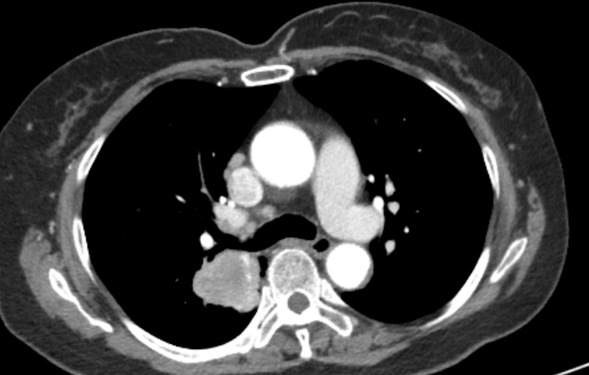

胸部CT:纵膈淋巴结肿大 双肺多发粟粒结节影

7组淋巴结肿大

4R组淋巴结肿大